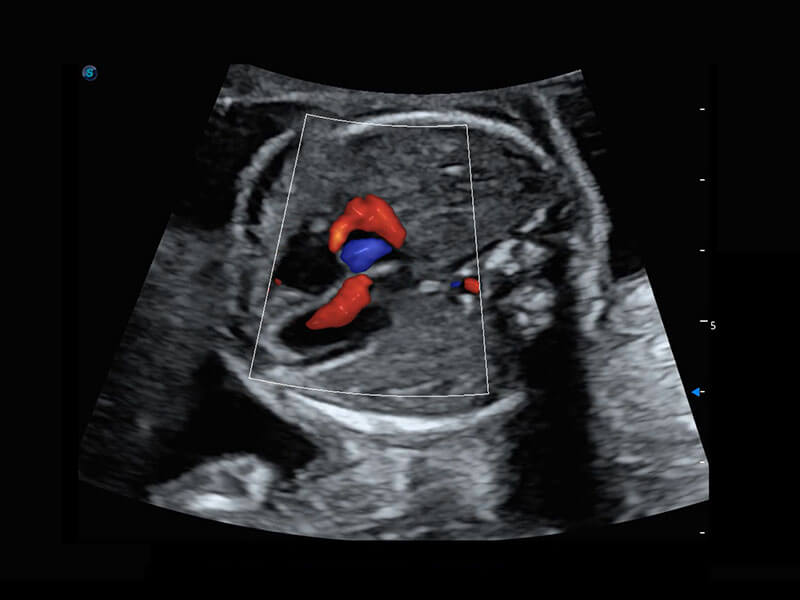

P60搭载一系列胎儿心脏成像技术,实现精细的胎儿心脏评估。

右室双出口